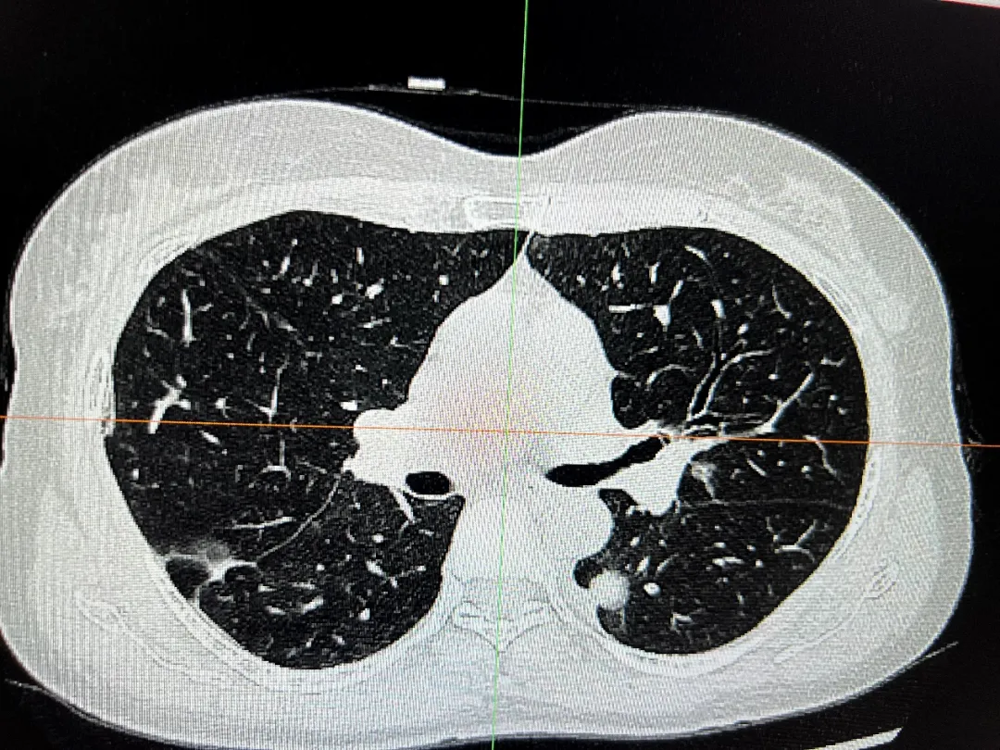

二、胸外科:高难微创,勇克双侧多原发肺癌

胸外科在复杂肺癌手术领域不断突破。一例55岁女性患者,CT发现双肺多发结节,高度怀疑多原发肺癌。面对传统分期手术创伤大、恢复慢的挑战,经多学科(MDT)充分评估、精密协作,胸外科团队勇于创新,成功为患者实施了“单孔胸腔镜下同期双侧肺癌根治术(右肺上叶切除+左肺下叶背段切除+双侧纵隔淋巴结清扫)”。手术一次完成,极大减少了患者痛苦与住院时间。术后病理证实为双侧原发性肺癌,分期分别为IIB期和IA2期。患者术后恢复迅速,第二天即可下床活动,并接受规范的靶向治疗(口服奥希替尼)。至今随访2年,无复发迹象,生活质量高。此案例彰显了我院胸外科在高难度、微创化、个体化肺癌手术治疗方面的卓越实力。

术前右侧胸部肿瘤

术前左侧胸部肿瘤